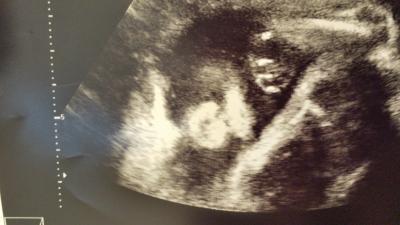

Huhu! Ich War heute bei 26+5 wieder beim doktor! Ist alles super! Die Kleine wiegt 1060 g.Endlich ist meine 1000g-zitterhürde überstanden... Ansonsten ist alles super und könnte nicht besser sein.diw fruchtwassermenge ist super,die Versorgung meiner kleinen Maus könnte gar nicht besser sein und sonst ist soweit auch sehr gut. Ich habe nur keine anderen Maße erfahren..aber,wenn sie schon so schwer ist,dann scheint es auch Größenmäßig alles in Ordnung zu sein.:-) Die kleine Maus hat auch gezeigt,dass man wunderbar mit Ultraschallköpfen boxen kann. Meine Ärztin hat es auch richtig gespürt. ;-) Ansonsten hatte ich heute den glucose-test. Lecker schmecker. ..:-/.fFreitag soll ich anrufen.;-) Das nächste mal muss ich am 11.3.hin.da wird das erste ctg gemacht. da freue ich mich drauf! Sie hat sich viel versteckt heute,aber ein Bildchen vom Gesicht in groß gab es.:-) mit schweinchennase!

Bild zu Heutiger Arzttermin - Forum für Mai - Mamis

Schade, dass Bild ließ sich nicht drehen..:-/ Dreht einfach euern Kopf nach links.dann seht ihr das Gesicht.:-) Ganz links das weiße ist die Stirn.Dadrunter sind die Augen.Das runde, weiße in der Mitte ist die Schweinchennase und dadruneter die Oberlippe.:-)Genuckelt wurde auch wieder.:-D.Das, was wie eine Tatze ausschaut, ist die Hand.:-P